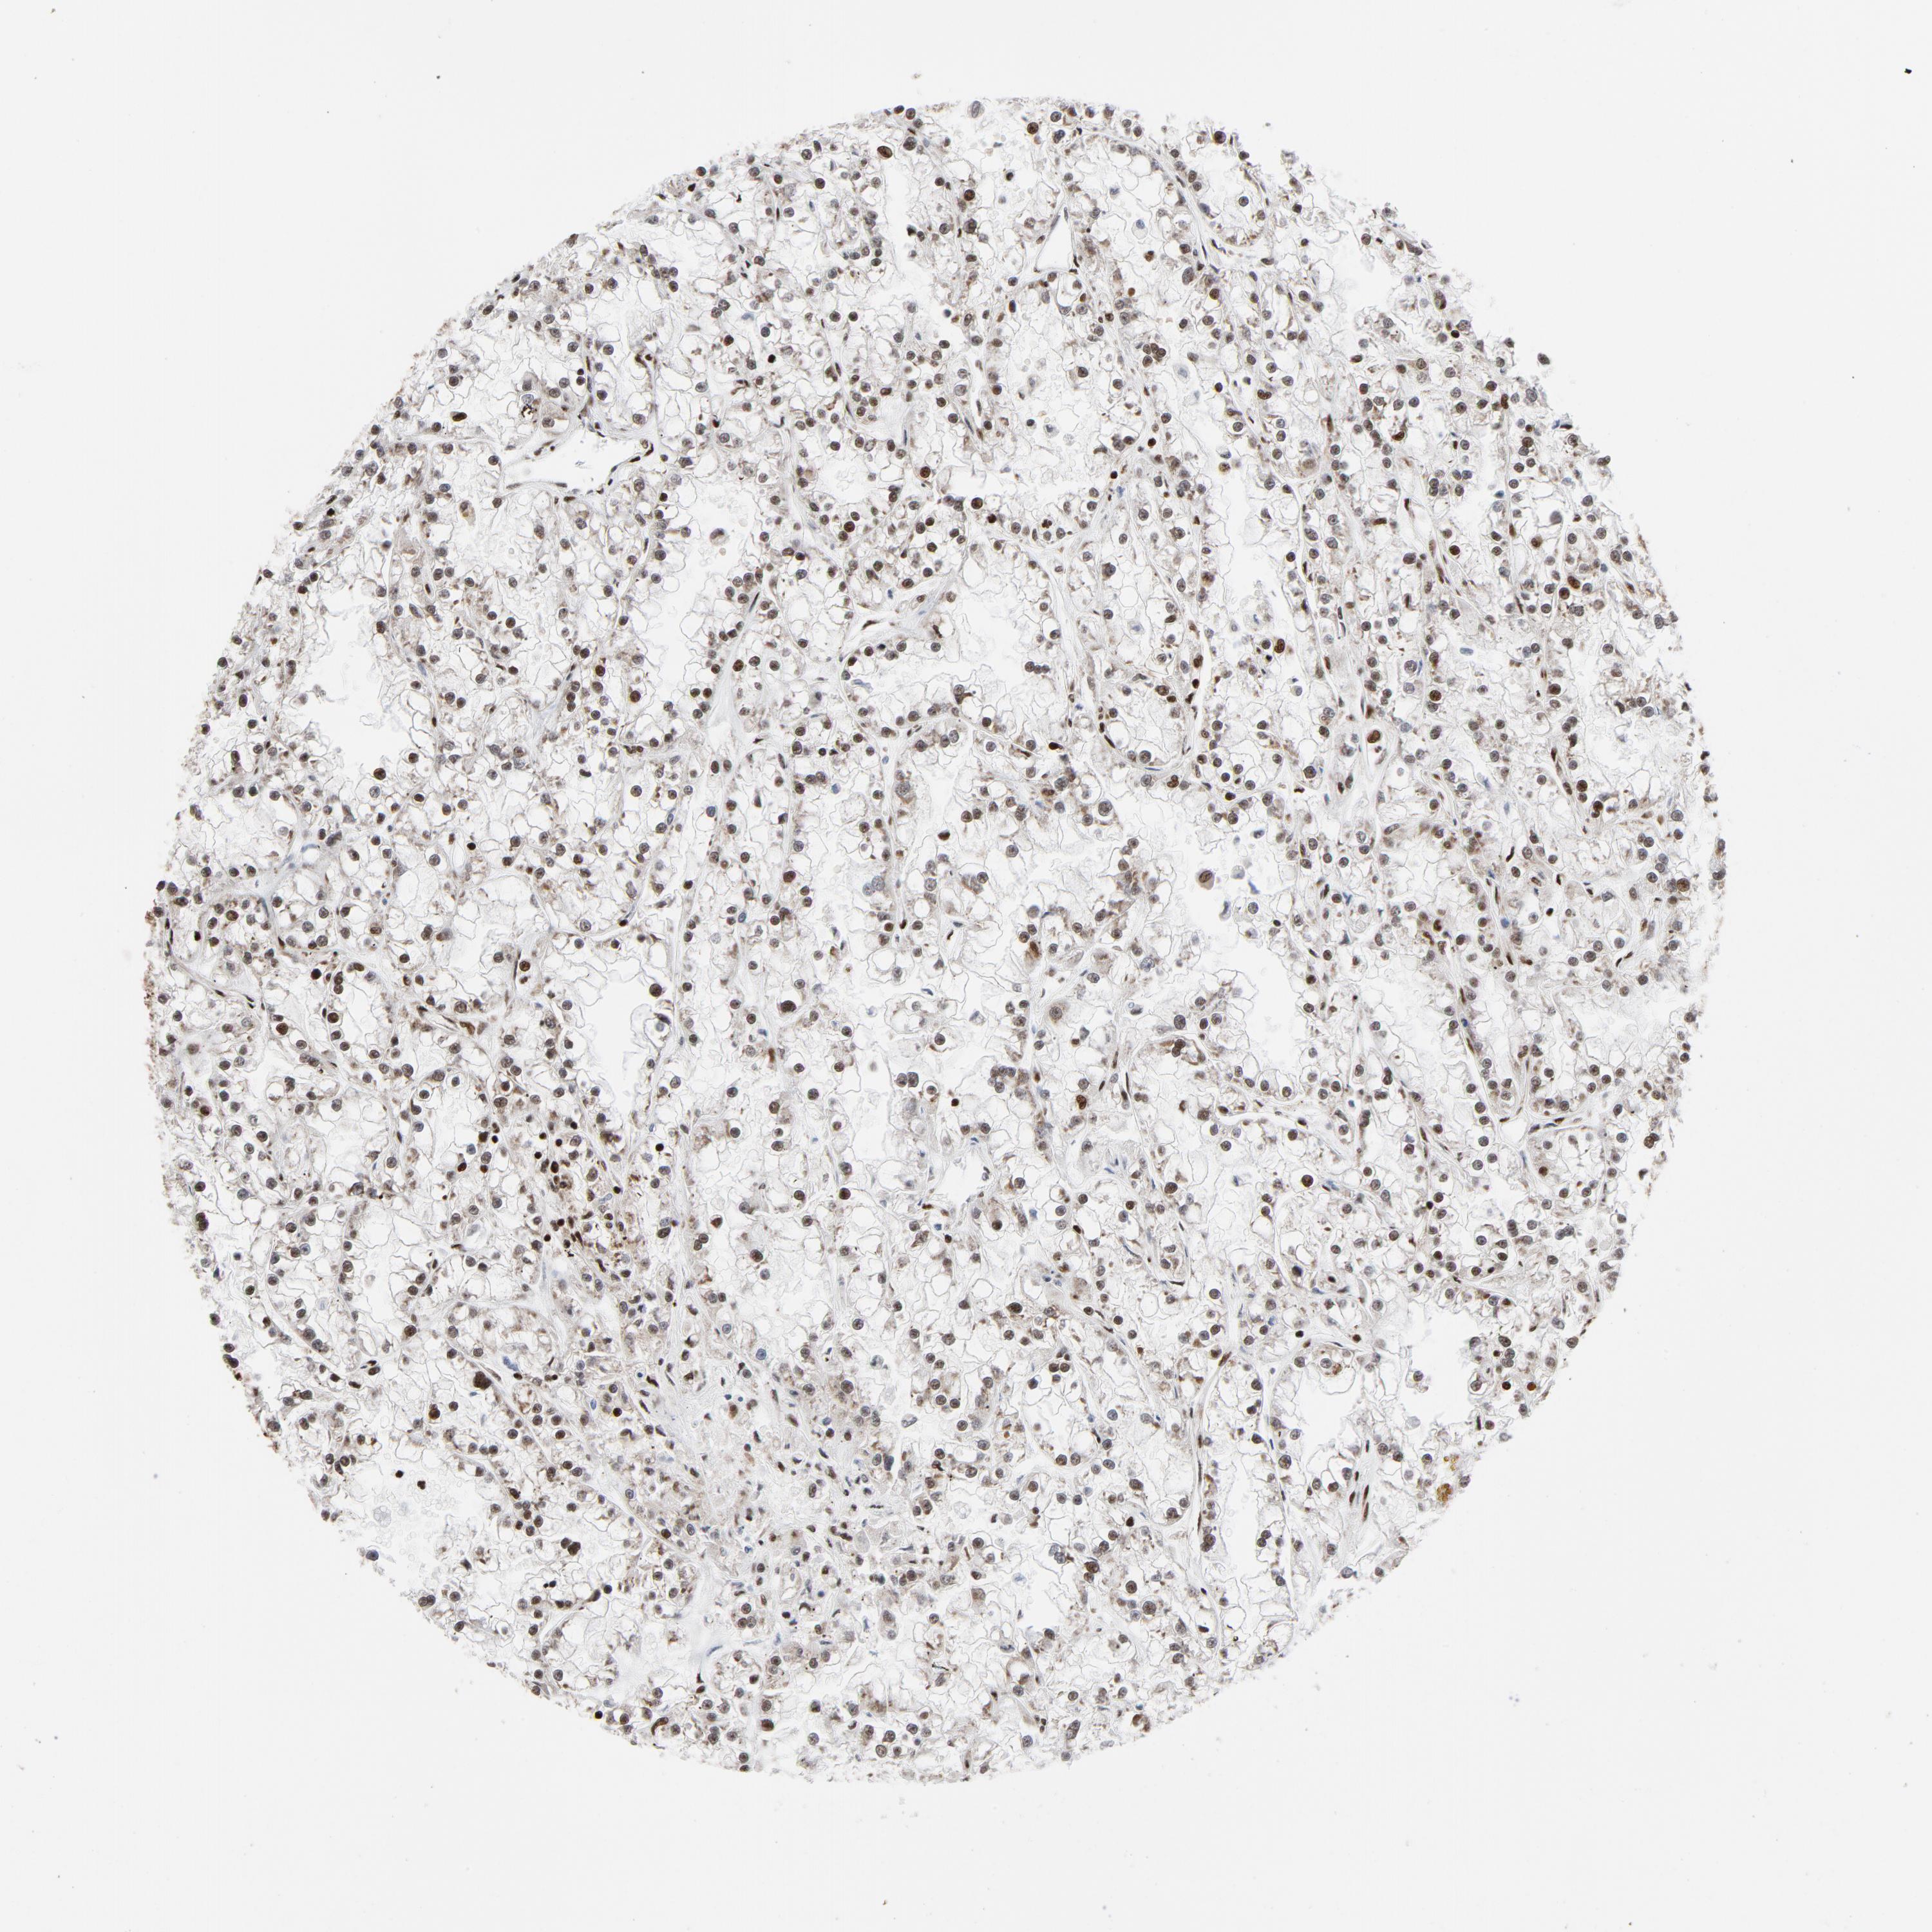

KIDNEY RENAL CLEAR CELL CARCINOMA (VALIDATION) - Interactive survival scatter ploti

The Survival Scatter plot shows the clinical status (i.e. dead or alive) for all individuals in the patient cohort, based on the same data that underlies the corresponding Kaplan-Meier plots. Patients that are alive at last time for follow-up are shown in blue and patients who have died during the study are shown in red.

The x-axis shows the expression levels (FPKM) of the investigated gene in the tumor tissue at the time of diagnosis. The y-axis shows the follow-up time after diagnosis (years). Both axes are complimented with kernel density curves demonstrating the data density over the axes. The top density plot shows the expression levels (FPKM) distribution among dead (red) and alive patients (blue). The right density plot shows the data density of the survived years of dead patients with high and low expression levels respectively, stratified using the cutoff indicated by the vertical dashed line through the Survival Scatter plot. This cutoff is automatically defined based on the FPKM cutoff that minimizes the p-score. The cutoff can be changed by dragging the vertical line or by entering a cutoff value in the square labeled "Current cut-off".

Under the Survival Scatter plot the p-score landscape (black curve; left axis) is shown together with dead median separation (red curve; right axis). Dead median separation is the difference in median mRNA expression between patients who have died with high and low expression, respectively. It is calculated as follows: median FPKM expression of dead patients with high expression - median FPKM expression of dead patients with low expression. This is intended to aid the user in visually exploring custom cutoffs and the associated p-scores and dead median separation.

Individual patient data is displayed and can be filtered by clicking on one or more of the category buttons on the top of the page. Categories describing expression level and patient information include: high, low, alive, dead, female, male and tumor stages. The scale of the x-axis can be toggled between linear and log-scale by clicking on the "x log" button. Mouse-over function shows TCGA ID, patient information and mRNA expression (FPKM) for each patient.

& Survival analysisi

Kaplan-Meier plots summarize results from analysis of correlation between mRNA expression level and patient survival. Patients were divided based on level of expression into one of the two groups "low" (under cut off) or "high" (over cut off). X-axis shows time for survival (years) and y-axis shows the probability of survival, where 1.0 corresponds to 100 percent.

NFYB is not prognostic in Kidney Renal Clear Cell Carcinoma (validation)

Best expression cut offi

Based on the FPKM value of each gene, patients were classified into two groups and association between prognosis (survival) and gene expression (FPKM) was examined. The best expression cut-off refers the FPKM value that yields maximal difference with regard to survival between the two groups at the lowest log-rank P-value. Best expression cut-off was selected based on survival analysis .

When clicking on this number, the vertical dashed line indicating cut-off, the interactive survival plot, and the Kaplan-Meier curve will be adjusted to show results based on the best expression cut-off.

: 23.31

Median expressioni

Median expression refers to the median FPKM value calculated based on the gene expression (FPKM) data from all patients in this dataset. When clicking on this number, the vertical dashed line indicating cut-off, the interactive survival plot, and the Kaplan-Meier curve will be adjusted to show results based on the median expression.

: N/A

Median follow up timei

Median follow up time refers to the median time (years) after diagnosis with this type of cancer, based on clinical data from all patients in this dataset.

P scorei

Log-rank P value for Kaplan-Meier plot showing results from analysis of correlation between mRNA expression level and patient survival.

N/A

5-year survival highi

5-year survival for patients with higher expression than the expression cutoff.

For melanoma and glioma, 3-year survival is shown.

5-year survival lowi

5-year survival for patients with lower expression than the expression cutoff.

TCGA RNA samplesi

RNA-seq data is reported as average FPKM (number Fragments Per Kilobase of exon per Million reads), generated by the The Cancer Genome Atlas (TCGA) .

Normal distribution across the dataset is visualized with box plots, shown as median and 25th and 75th percentiles. Points are displayed as outliers if they are above or below 1.5 times the interquartile range. FPKM values of the individual samples are presented next to the box plot.

Average pTPM 23.9

Number of samples 100